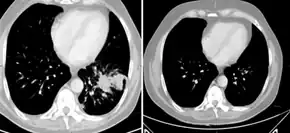

Individual with metastatic castration-resistant prostate cancer after initiation of abiraterone result in response 6 months after starting

Abiraterone acetate is used in combination with prednisone, a corticosteroid, as a treatment for mCRPC (previously called hormone-resistant or hormone-refractory prostate cancer).[3][16][7][6] This is a form of prostate cancer that is not responding to first-line androgen deprivation therapy or treatment with androgen receptor antagonists. Abiraterone acetate has received Food and Drug Administration (FDA) (28 April 2011), European Medicines Agency (EMA) (23 September 2011), Medicines and Healthcare products Regulatory Agency (MHRA) (5 September 2011) and Therapeutic Goods Administration (TGA) (1 March 2012) approval for this indication.[3][16][7][6] In Australia it is covered by the Pharmaceutical Benefits Scheme when being used to treat castration-resistant prostate cancer and given in combination with prednisone/prednisolone (subject to the conditions that the patient is not currently receiving chemotherapy, is either resistant or intolerant of docetaxel, has a WHO performance status of <2, and his disease has not since become progressive since treatment with PBS-subsidised abiraterone acetate has commenced).[17]